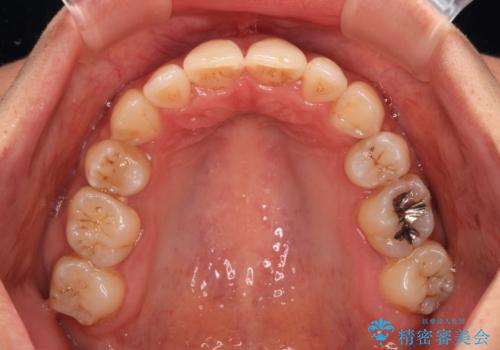

- 八重歯と上下前歯のでこぼこを気にして来院された患者様です。

上下前歯部叢生のスペース獲得のため、上下顎左右小臼歯各1歯(計4本)を抜歯して、ワイヤー装置にて矯正治療を行うこととしました。

上下の正中位置が大きくずれていたため、上下正中が合わないまま終了することが予想されましたが、思っていた以上にスムーズに歯が移動し、満足いただける仕上がりとなりました。